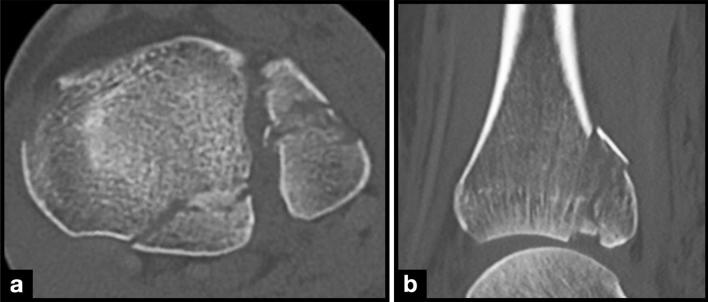

复杂的踝关节骨折常包括后踝(PM)。尽管在诊断和治疗策略方面取得了进展,但 PM 骨折的累及仍然会导致预后更差。尽管在最常见的 PM 骨折分类中没有纳入,但存在间插骨块(ICF)会使治疗变得复杂。本研究旨在描述 PM 骨折中 ICF 的发生率、形态和位置。

在 135 名患者中,55 名(41%)存在 ICF。与无 ICF 的患者相比,有 ICF 的患者年龄更小,PM 更常接受手术治疗。当存在 ICF 时,更常采用后外侧入路。几乎所有的 ICF 都位于后外侧(58%)和后中央(35%)区域。大多数骨块位于 Bartoníček/Rammelt 类型 2 骨折中,这是最常见的骨折类型。Bartoníček/Rammelt 类型 3 骨折中 ICF 的相对频率最高。

ICF 常存在于 PM 骨折中,但未纳入任何常见分类。它们通常存在于年轻患者中,并与更复杂的 PM 骨折相关。由于它们可以使主要骨块的复位复杂化,并且可能需要直接暴露来恢复关节的一致性,因此在 PM 骨折分类中应考虑 ICF。由于其位置,大多数 ICF 可以通过后外侧入路进行处理。